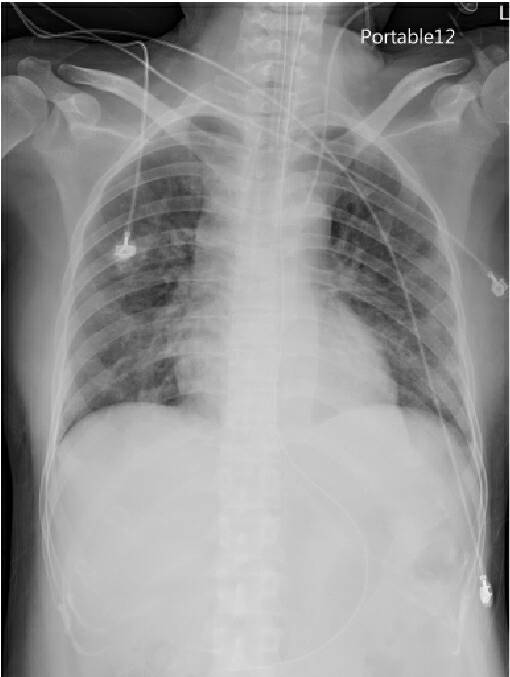

在接受治療後,原肺部發炎的泛白已消失無蹤(示意圖)

執行裝置葉克膜的羅東博愛醫院心臟血管外科主任賴韋良表示,個案到院時肺部已呈現嚴重呼吸衰竭,即便已經使用呼吸器,氧氣濃度調到百分之百,但是他的血氧濃度還是不到60%,才會使用葉克膜支持婦人的心肺功能。在醫療團隊的照顧下終於在順利拔除管路回到呼吸照護中心休養,目前已康復出院。

羅東博愛醫院盧進德副院長表示,此個案在發病前未接踵流感疫苗,雖為併發重症病患,進行過兩次流感快篩,皆顯示陰性,但由於已出現肺炎情形,因此推估應為類流感引起,緊急裝置葉克膜並送進ICU加護病房照護,並及時施以克流感藥劑治療。